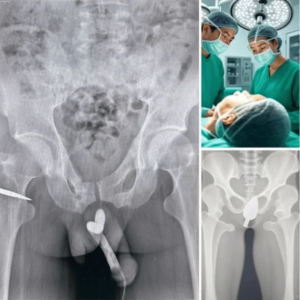

Teen Hospitalized After Risky Experiment: A Wake-Up Call About Health, Safety, and Awareness

In recent days, a story has captured widespread attention on social media and health forums. A teenage girl was rushed to the hospital after an alarming incident…